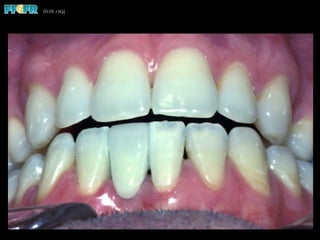

Affect of Incisally

Positioned Gingiva

Produces Short

Clinical Crowns

Affect of Incisally PositionedGingiva Produces Short Clinical Crowns